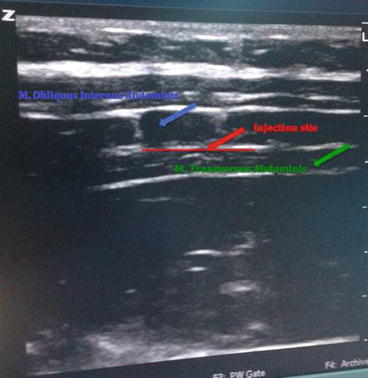

TAP block is a regional anesthesia technique providing analgesia on the frontal abdominal wall up to the parietal peritoneum including the muscles and skin. Compared to modern techniques it is not used much in practice, despite its high-success rate and relatively low-complication risk [34]. Subumbilical anesthesia of the abdominal frontal wall is achieved by applying local anesthetic in a high volume (20 ml) with a special needle together with ultrasound between the internal oblique muscle on lumbar Petit triangle and transverse abdominis muscle. When the oblique subcostal TAP block is added, the whole abdominal frontal wall is anesthetized [1–34].

Postoperative pain treatment is worrisome for both surgeons and patients. In order to achieve a painless postoperative period, many methods such as local anesthetic infiltrations, epidural analgesia, peripheral nerve disorders, and intravenous patient-controlled analgesia (iv-PCA) are used. TAP block takes its place as a safe and effective method that can be applied easily under ultrasound guidance to reduce postoperative pain in lower abdominal region [35]. It is more important for patients with high risks such as obstructive sleep apnea since it reduces the need for postoperative narcotic drugs [35, 36]. In the labeled pictures below, some examples of ultrasound-guided TAP block are shown (Pictures 2.1, 2.2, and 2.3).

Picture 2.1

Ultrasound-guided TAP block (From the right lumbar Petit triangle)

Picture 2.2

Ultrasound-guided TAP block (From the left lumbar Petit triangle)

Picture 2.3

Ultrasound vision at TAP block